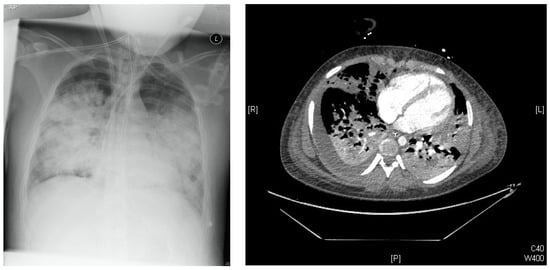

2.3.1. Clinical Response and Disease Severity

2.3.2. Virologic Response

2.3.3. Biomarker Response